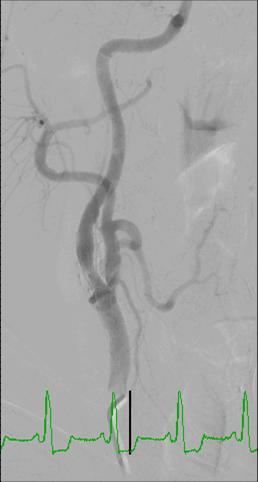

Angiography for the diagnosis of carotid artery stenosis

Angiography is the traditional ‘gold standard’ for the imaging of blood vessels. Direct angiography offers the best means for visualization of carotid artery lesions and overcomes most of the limitations that were listed for the other methods. The main disadvantages of carotid artery angiography include:

- It is an invasive procedure

- It exposes patients to ionizing radiation and contrast material

Therefore, nowadays angiography is utilized only when the non-invasive methods gave inconclusive results.

CT scan for carotid artery imaging

CT scan (CTA – CT angiography) offers a very reliable and accurate method for visualization of carotid artery stenosis. It has a sensitivity and specificity of 97-99{8ceaa46882e4d49283ff23b35262537230ad541262f55a031ead545e66522058} compared with angiography. Being a fast scan, CT is less susceptible to artifacts caused by patient movement. The most common way to measure carotid artery stenosis by CT (or angiography) is by utilizing the NASCET criteria. In this method the stenosis is expressed by the following formula:

Stenosis({8ceaa46882e4d49283ff23b35262537230ad541262f55a031ead545e66522058})=(1-R/D)*100

R – Minimal residual lumen at the level of stenosis, D – Diameter of the more distal internal carotid artery.